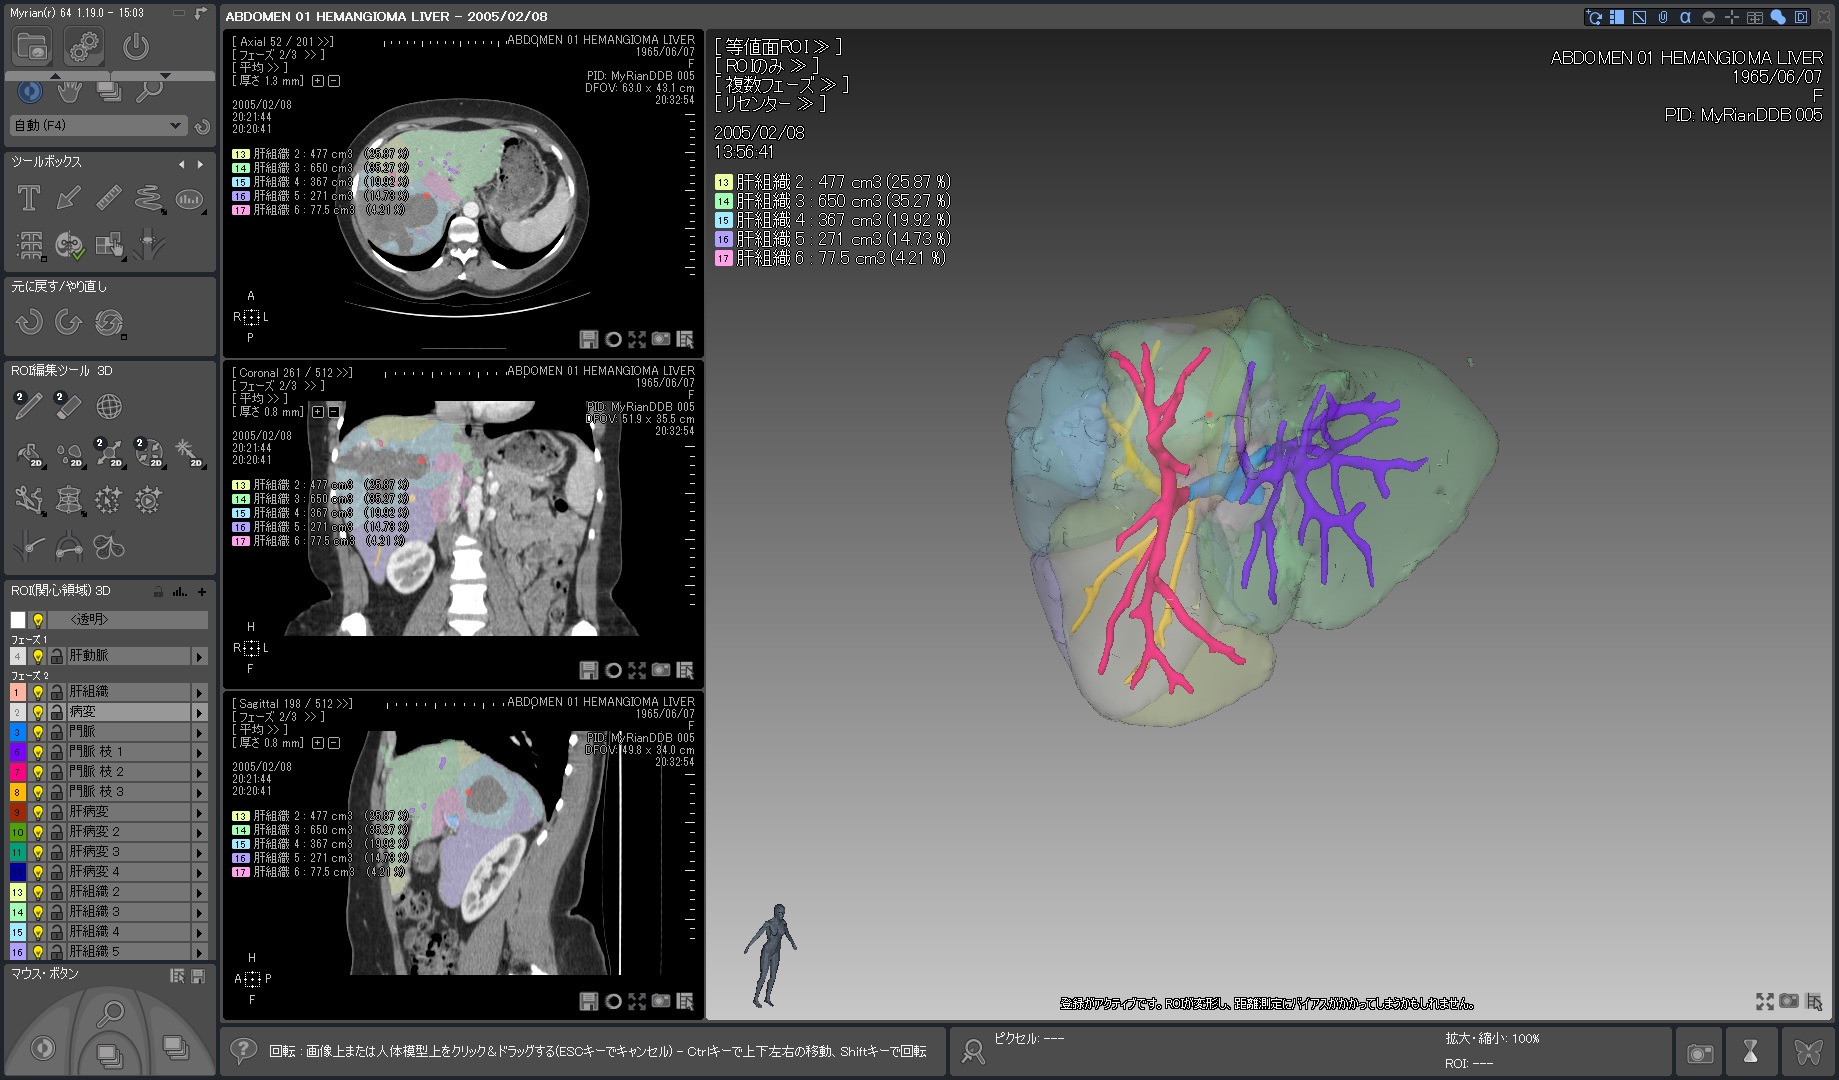

Myrian®XP-Liver 肝臓アプリケーション

世界的な実績と評価を得ている、肝臓解析と手術計画用ソフトウェア

独自に開発された、正確な非剛体レジストレーションと優れたセグメンテーション・アルゴリズムにより肝血管系、肝実質、腫瘍などを数秒で抽出します。

3D PDFによる立体表示ではコミュニケーションの向上に寄与するでしょう。

当製品は3D業界の先駆けとして、世界トップの施設で使用されています。

| 2.肝臓血管系の半自動抽出 |  |

| 3.血管支配域の表示 |  |